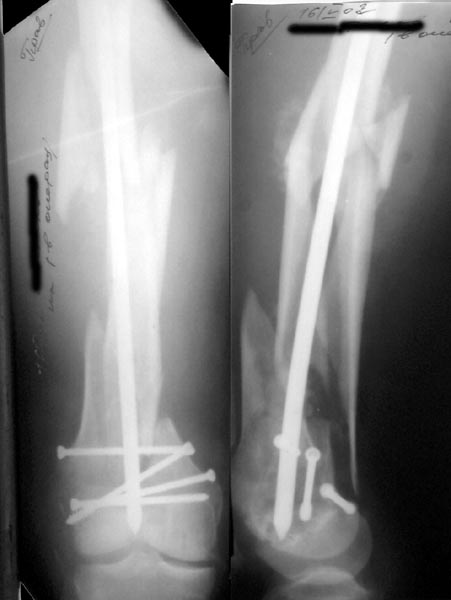

Re: Многооскольчатое бедро

Alexander Chelnokov 16 Май 2002, 17:30

А> Попробуй ретроградно интрамедуллярный гвоздь с блокированием

Нету у нас (пока?) гвоздей для ретроградного введения. Доводилось слышать, что можно любые гвозди вводить ретроградно, но как-то не

получается пока преодолеть психологический барьер. В основном потому, что не могу для себя уяснить преимущества введения через колено

обычного UFN. Или, как коллеги из Индии рассказывали, кое-кто вводит UTN в бедро ретроградно.

ЛА> и увеличенным количеством винтов дистально или как ты любишь miss

ЛА> a nail.

Да, примерно так и сделали. Надо было, пожалуй, кончик гвоздя еще спилить, чтобы отверстие было еще дистальнее. Англоязычные коллеги еще

советовали винты в передне-заднем направлении вводить, но что-то не увидел, где там подходящее место.

Since it was done closed the shaft will heal or at worst need an exchange IMN.

Nice job.

Тем и отличается специальный стержень, что там все удобно. Кроме того я еще закрываю пробкой - костной место введения, т.е. сначала вскрываю канал полой фрезой. Для стабильности раннего движения в суставах этой конечности и передвижения в простравнстве существуют ортезы с шарнирами. Надеюсь длина конечности правильная.